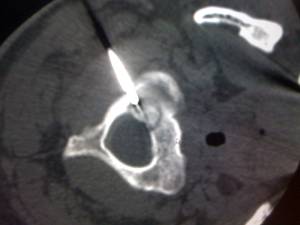

图1:CT定位下穿刺取活检 图2:定位

图3:射频电极置入 图4:取活检